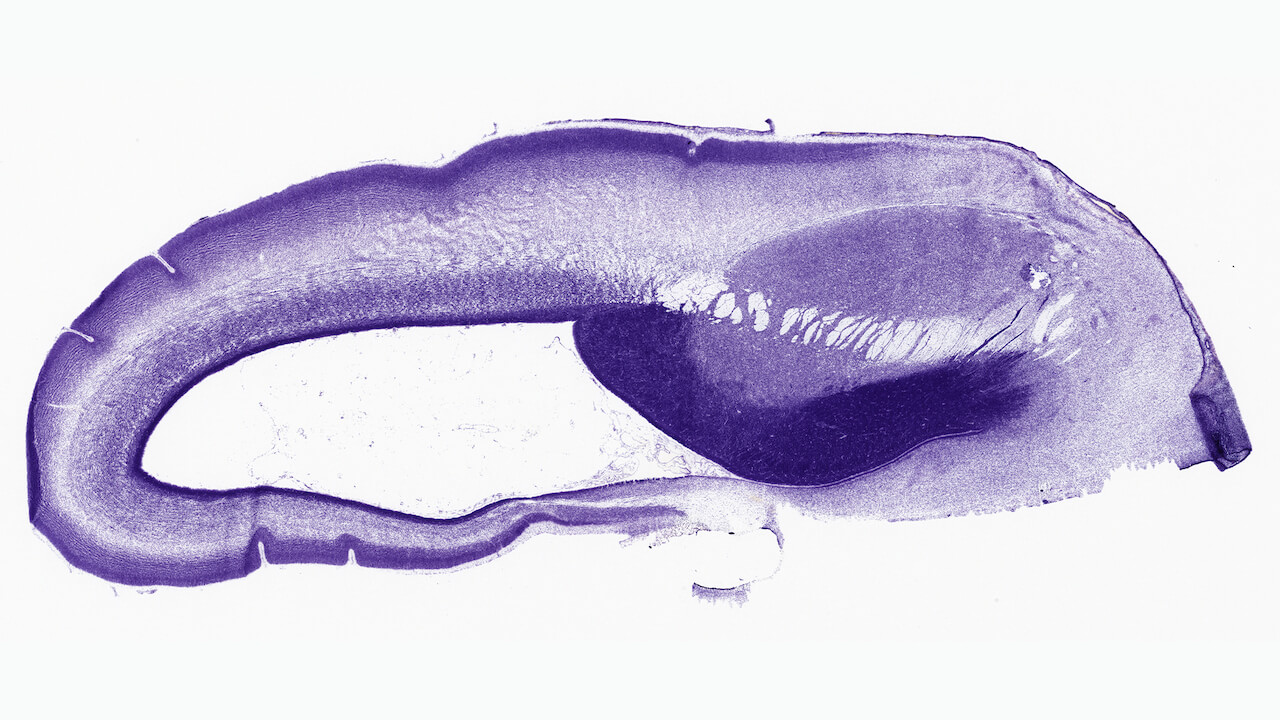

The study, led by researchers at Yale University, the Allen Institute and the University of Southern California and published last week in the journal Science, looked at tissue from 60 different postmortem brains, ranging in age from early in the prenatal period to a 64-year-old adult. The work came about in part through the BrainSpan consortium, a collaborative effort funded by the National Institutes of Health to map genes in the developing human brain.

The research team looked at the activity patterns of all our approximately 20,000 genes in these brain samples, either cell by cell, or across 16 different regions of the brain to map how gene activity tracks with human brain development.